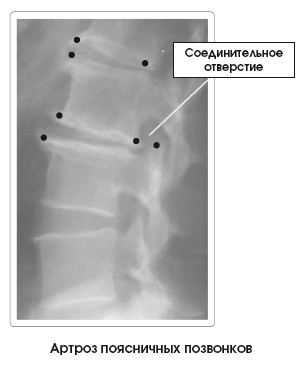

Для оценки состояния пациента применяют методы функциональной диагностики (рентген), объективного и субъективного обследования.

Иллюстрация к книге — Диагностика и лечение позвоночника. Уникальная система доктора А. М. Уриа [i_271.jpg]

Костные деформации (), называемые остеофитами, шпорами или пиками костей, характеризуют данное заболевание. Они бывают выраженными в той или иной степени в зависимости от уровня прогрессирования артроза. В зависимости от локализации процесса, размера и потери объема диска могут раздражаться и повреждаться структуры мягких тканей, такие как нервы, проходящие через соединительные отверстия, или межпозвоночные диски.